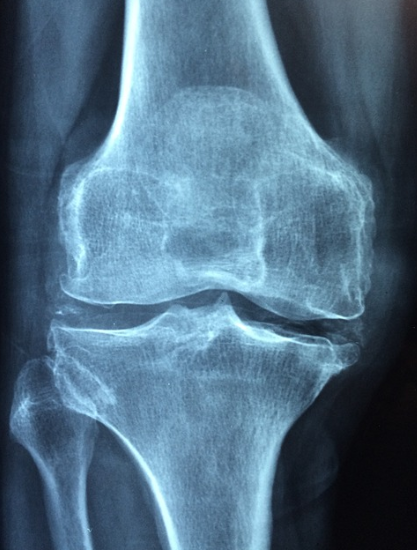

콘드로이친은 관절 연골을 구성하는 중요한 성분으로, 관절의 수분 유지와 탄력성을 증가시키는 역할을 합니다. 특히, 콘드로이친 1200mg은 관절 통증과 염증을 감소시키는 데 효과적이며, 장기적인 복용을 통해 관절의 기능을 향상시킬 수 있습니다. 관절염 환자에게 콘드로이친 1200mg 복용은 통증 완화뿐만 아니라 연골의 감소를 억제하고 염증을 줄이는 데 도움을 줄 수 있습니다.

콘드로이친의 효능은 여러 연구를 통해 입증되었습니다. 예를 들어, 하루 콘드로이친 1200mg을 복용하는 것이 관절 통증 감소에 효과적이라는 연구 결과가 있습니다. 콘드로이친 1200mg은 특히 관절의 염증을 완화하고, 관절 연골의 건강을 지원하는 데 중요한 역할을 합니다.